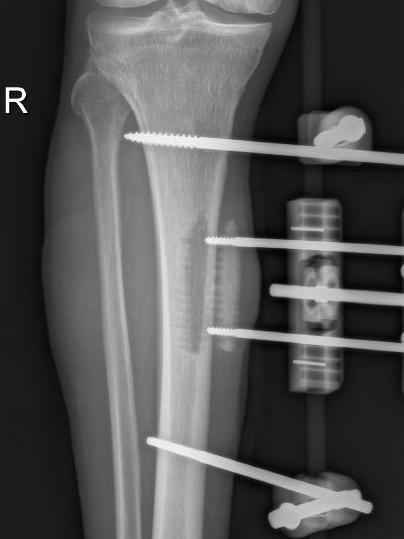

多年来,贵州航天医院各科室紧跟医学前沿,不断强技术、补短板,大力开展新技术、新项目,完成了许多高精尖、高难度、本地区“首例”的技术,填补了医院医疗技术空白,满足了群众日益增长的医疗需求。 贵州航天医院骨科率先在遵义地区开展骨搬移技术,截至目前,已治愈慢性骨髓炎、感染性骨不连、骨缺损、脉管炎、糖尿病足患者200余例,糖尿病足治疗保肢率达到98%。 本期,我们将为大家带来骨科特色技术——骨搬移技术(Ilizarov)。 案例分享 一名59岁的患者,身患糖尿病12年,在来我院3个月前出现了右脚溃烂的症状,来院就诊时,患者的右脚十分红肿,右脚脚趾坏死,伤口处不断流出黑红色脓液,情况十分严重。在接诊到患者时,骨科专家团队高度重视,立刻为患者完善了CT血管造影(CTA)等相关检查,诊断为:2型糖尿病,糖尿病周围血管病变,右糖尿病足。 术 前 考虑到患者情况比较严重,为最大限度保证患者肢体完整,科室专家团队进行了严格的讨论评估,为患者制定了骨搬移技术治疗方案,在征得患者及其家属的同意后,成功通过搬移骨块为患者进行治疗,促进患者病变肢体血管再生。 胫骨横向骨搬移外架固定 清除感染病灶 术后调节外架,通过搬移骨块 促进患肢血管再生 患者在术后三周前来换药,观察到感染得到进一步控制;术后六周复查,患者病变处已愈合,进行CT血管造影(CTA)后可明显观察到足部血管再生。 术后3周 术后6周愈合 CT血管造影见足部血管再生 糖尿病患者全身与局部的问题互为影响,形成恶性循环,糖尿病足溃疡创面迁延不愈,常见干性坏疽、湿性坏疽、趾坏死、深且大的溃疡以及骨髓炎等症状,还可导致脓毒血症,以往为保全生命,患者被迫选择一次或多次截肢。骨搬移技术的发展进步,能在血糖有效控制、局部有效清创下,有效促进患肢微血管再生,改善患肢血供,达到糖尿病足更快治疗康复的目的,并能根据病变情况最大限度的保障患者肢体完整。 什么是骨搬移技术 骨搬移技术是通过使用专用的骨外固定器固定骨段,每天缓慢牵拉,在牵拉搬移过程中,骨段尾部形成新骨及新的软组织,从而修复骨骼缺损及软组织缺损。是治疗大段骨缺损、骨不连、骨感染、肢体畸形的金标准方法,也用于治疗脉管炎、糖尿病足等肢体缺血性疾病。 骨感染缺损 切除感染段 搬移骨段 新骨形成 骨感染根治愈合 骨搬移技术原理 生物组织在持续、稳定、缓慢牵拉下,能刺激细胞分裂、组织再生,骨外固定技术运用该原理,通过持续缓慢调节外固定器形成牵拉张力,促进牵引成骨与相邻组织再生,如神经、血管、肌肉、皮肤等再生,达到治疗大段骨缺损、肢体缺血如糖尿病足等疾病的目的。 骨搬移技术优势 (一)除治疗骨缺损、骨不连外,有更广的适用范围,利用组织再生、血管再生等特性,能大量运用于肢体畸形的矫形、糖尿病足等的治疗。 (二)治疗效果确切,重建肢体外型和功能,极大降低截肢率和残疾率。 (三)明显提高了患者生活质量,极大减轻其家庭及社会负担。 肢体畸形的矫形 慢性骨髓炎 骨段切除 术后1年 濒临截肢的脉管炎术后6周 难愈创面术后3周 贵州航天医院骨科 专家团队 赵学平 骨科主任 主任医师 临床擅长:从事骨科临床工作30余年,对骨科常见疾病的诊治具有丰富的临床经验。 世界中医药联合会脊柱康复专业委员会常务理事,中华中医药学会整脊分会常务委员,中国中西医结合学会骨伤科分会肢体矫形功能重建与康复专家委员会常务委员,中国研究性医院学会骨科创新与转换专业委员会关节外科学组保髋工作委员会常委,中国康复技术转化及发展促进会骨外科与康复技术转化专业委员会常务委员,泛珠三角区域运动医学联盟(PPRD-SMA)理事会常务理事,中国研究型医院学会运动医学专业委员会委员,贵州省中医药学会整脊分会副主任委员,贵州省中西医结合学会银质针专业委员会副主任委员,贵州省康复医学会骨与关节专业委员会常务委员,贵州省人民医院骨科专科联盟常务理事,贵州省康复医学会骨内科专业委员会常务委员,中华医学会贵州省骨科学会委员,贵州省康复医学会脊柱脊髓专业委员会常务委员,贵州省运动医学分会委员,贵州省康复医学会骨与软组织肿瘤专业委员会委员,遵义市医学会创伤分会副主任委员,贵州省康复医学会骨内科专业委员会遵义地区分会常务委员,遵义市医疗事故鉴定、伤残鉴定、工伤鉴定、司法鉴定专家。 长期从事骨科临床研究及教学工作,在国家级、省部级杂志发表论文20余篇,SCI论文2篇,参与主编骨科专著2部,主持省部级科研项目2项,参与指导省部级、市级科研项目6项。 陈明勇 骨科副主任 副主任医师 临床擅长:从事创伤骨科工作约20年,对骨缺损、骨不连、骨肿瘤、肢体畸形等的肢体矫形重建及功能重建,慢性化脓性骨髓炎的根治治疗、糖尿病足的保肢治疗、快速康复理念(ERAS)下的老年骨折的诊治,四肢复杂骨折的诊治,四肢骨折等微创手术治疗具有丰富的临床经验。 2004年毕业于遵义医学院临床专业,曾在中国人民解放军总医院、广西医科大学第一附属医院、上海第六人民医院骨科进修。中国中西医结合学会骨伤科专业委员会横向骨搬移治疗糖尿病足及微血管网再生学组首届委员,遵义市医学会创伤分会常务委员。 瞿 辉 骨科 副主任医师 临床擅长:对骨科的常见病、关节外科、脊柱外科及运动医学疾病的诊治具有丰富的临床经验,熟练掌握骨科手术操作技术。 毕业于遵义医学院临床医学系,2005年前往广州中山大学第一附院骨显微医学部进修学习,2011年前往成都华西医院进修学习,并多次在省内外学习骨科相关知识,是中华医学会骨科分会会员。 赵兴东 骨科 主任医师 临床擅长:擅长骨科的常见病及各种创伤、四肢骨折创伤修复、骨感染、手足疾病的诊治和手足体表畸形的矫形整复,熟练掌握骨科四肢骨病及创伤的手术操作技术,尤其在四肢关节复杂性损伤、手足外伤、组织缺损创面、难治创面的皮瓣修复方面及平足、高弓足矫形方面及四肢慢性疼痛诊治、康复方面具有丰富的临床经验。 硕士研究生,毕业于遵义医学院临床外科系,2015年前往山东省立医院手足外科进修学习;遵义市医学分会创伤分会第一、二届委员,遵义市手外科医学会第二委届员会常务委员;在省级及省级以上期刊发表文章9篇,参编著作2部,参与主持并完成市级课题1项,参与市级课题2项、省级课题1项。 张俊凯 骨科 副主任医师 临床擅长:从事骨科临床工作28年,对创伤骨折、骨感染、骨缺损、骨不连等外科诊治,四肢骨折的微创手术治疗,四肢复杂骨折(如关节内粉碎性骨折、多发骨折等)的损伤控制及手术治疗等具有丰富的临床经验。 1995年毕业于遵义医学院临床专业,2009年前往复旦大学附属医院骨科进修1年。 卢懿明 骨科 副主任医师 临床擅长:从事骨科工作18年,对创伤骨折、四肢骨折的微创手术治疗、四肢复杂骨折(如关节内粉碎性骨折、多发骨折等)的损伤控制及手术治疗,尤其是髋部骨折的PFNA等微创技术,踝关节骨折、膝关节周围骨折的Mipo微创技术等具有丰富的临床经验,开展了4项新技术,发明6项新型专利技术。 2005年毕业于遵义医学院临床专业,2017年,前往南方医科大学第三附属医院骨科进修半年,回院后运用Mipo技术对骨干骨折及干骺端骨折的治疗技术,同时积极开展骨盆骨折、髋臼骨折腹直肌外侧切口的应用;发表了多篇专业论文,经常参与省内外学术交流会授课,获得医院荣誉称号多个。 邬夏荣 骨科 副主任医师 临床擅长:从事骨科工作16年,对四肢复杂骨折、骨肿瘤的诊治,尤其是足踝创伤、慢性踝关节损伤、平足症等诊疗具有丰富的临床经验。 2006年毕业于遵义医科大学临床医学专业,曾在陆军军医大学西南医院进修学习,发表多篇骨科学术论文。 余德怀 骨科 副主任医师 临床擅长:从事骨科工作10余年,对运动医学、骨关节、脊柱外科常见病、多发病的诊治具有丰富的临床经验。 硕士研究生,2011年毕业于遵义医学院临床医学专业,曾前往遵义医科大学附属医院运动医学专业进修学习;是贵州省医学会运动医学分会青年委员,西部关节镜联盟委员;发表多篇骨科学术论文。 冯 乾 骨科 副主任医师 临床擅长:从事骨科工作近20年,熟练掌握骨科多发病及常见病的诊治,尤其对脊柱退变性疾病的诊断及治疗具有丰富的临床经验,主要研究脊柱微创相关治疗方式,能熟练开展椎间孔镜及VBE。 曾前往北京大学第三医院进修学习疼痛及椎间孔镜、首都医科大学友谊医院专业进修脊柱内镜;是贵州省康复医学会第三届脊柱脊髓专业委员会委员;发明专利3项、发表脊柱外科专业论文多篇。 张艳金 骨科 副主任医师 临床擅长:从事骨外科工作16年,对复合伤、多发伤的救治、四肢骨干骨折、关节周围骨折、骨肿瘤、骨髓炎等诊治具有丰富的临床经验。 中共党员,硕士研究生,2006年本科毕业于山西医科大学第二临床医学院,2011年研究生毕业于北京军区总医院;在“老年COPD患者合并髋部骨折的诊治”国际合作课题组研究两年,在老年髋部骨折的诊治方面具有丰富的经验,并发表论文6篇;承担遵义市级课题1项;承担遵义医科大学的临床教学工作,获得遵义医科大学优秀带教老师荣誉。编撰有《骨科疾病诊疗精粹》一书,开展2项新技术,编撰地方规范《务川自治县创伤骨科常见疾病诊疗规范》一书。 赵小锋 骨科 副主任医师 临床擅长:从事骨科临床工作11年,对骨科常见病、多发病诊疗有较为丰富的临床经验,擅长脊柱相关疾病诊断及治疗,尤其是颈、腰、腿疼痛疾病诊断及治疗,擅长胸腰椎骨折微创经皮穿刺内固定术、经皮穿刺椎体成形术、经皮穿刺脊柱内镜下腰椎间盘摘除术、单纯开创腰椎间盘摘除术、腰椎滑脱复位椎间植骨椎融合内固定术、腰椎管狭窄减压融合内固定术及人工髋、膝关节置换术等。 2012年毕业于遵义医学院外科学专业硕士研究生,2019年参加“遵义市115医学人才精英计划”于上海交通大学第一附属医院培训学习,2023年于北京大学第三人民医院脊柱外科进修学习,曾获得遵义市优秀医师荣誉称号。 遵义市手外科第一届委员,遵义市医学会创伤分会第一届委员,遵义市医学会创伤分会第二届委员,贵州省康复医学会第三届脊柱脊髓专业会委员,遵义市医学会烧伤与整形外科学分会委员,发表论文5篇,其中国家级核心期刊1篇,SCI论文1篇,主持市级课题1项并结题,参与市级课题2项。 贵州航天医院骨科简介 基本情况 贵州航天医院(原3417医院)骨科组建于1968年,前身是以创伤和断肢(断指)再植闻名于世的上海市第六人民医院骨科,中国断肢(断指)再植的奠基者、中科院院士陈仲伟等著名专家、学者多次莅临科室指导医疗、教,是贵州省最早拥有专业骨科技术科室之一,在70年代开展了贵州省首例断肢(断指)再植手术。组建50余年来,诊治患者已逾百万,挽救了无数的伤病员,成为了保障遵义地区人民群众健康的重要支撑。 经过几代人的不懈努力,今天的骨科,已由创伤骨科发展至骨病、骨肿瘤、骨结核等领域,现有脊柱外科、关节外科、四肢创伤、手足外科四个亚专科,成为了集医疗、教学、科研于一体的综合学科,是贵州省临床重点专科、遵义市临床重点专科、遵义市骨科临床医学中心、遵义市基层骨科专科联盟理事长单位。 科室目前开放床位110张,共有医护人员50余人,副高级以上专家18人,硕士研究生15人。拥有一流骨科医疗设备多台,每年不定期选派优秀技术骨干到全国各大知名医学院校进修、学习、参观、交流,并邀请国内、国外知名专家教授来院进行交流、指导,通过不断引进国内外先进的诊疗技术,科室医疗技术水平稳步提升,为广大人民群众提供了优质的医疗服务。 专科特色 骨一科 (一)骨缺损、骨不连的肢体与功能重建 胫骨横向骨搬移技术治疗糖尿病足: (二)慢性骨髓炎的根治治疗 (三)肢体缺血性疾病如糖尿病足、脉管炎的保肢治疗 (四)皮瓣修复 (五)复杂创伤的治疗 (六)老年髋部骨折及小儿骨折快速手术 老年髋部骨折: 骨二科 (一)胸腰椎骨折微创经皮椎弓根螺钉固定术 (二)老年性骨质疏松性患者腰椎滑脱脊柱内固定术(骨水泥螺钉) (三)V形双通道脊柱内镜技术(VBE)腰椎融合术治疗腰椎退行性疾病 (四)老年性骨质疏松性骨折(PVP/PKP)术 (五)人工髋关节置换术 (六)双侧股骨头坏死人工全髋关节置换 (七)右侧全髋置换术后假体周围骨折翻修 (八)人工膝关节置换术 (九)人工膝关节假体松动翻修 (十)关节镜技术 传统手术切口 关节镜技术切口 诊疗范围 骨一科 1.四肢创伤、矫形。 2.手、足踝外科。 骨二科